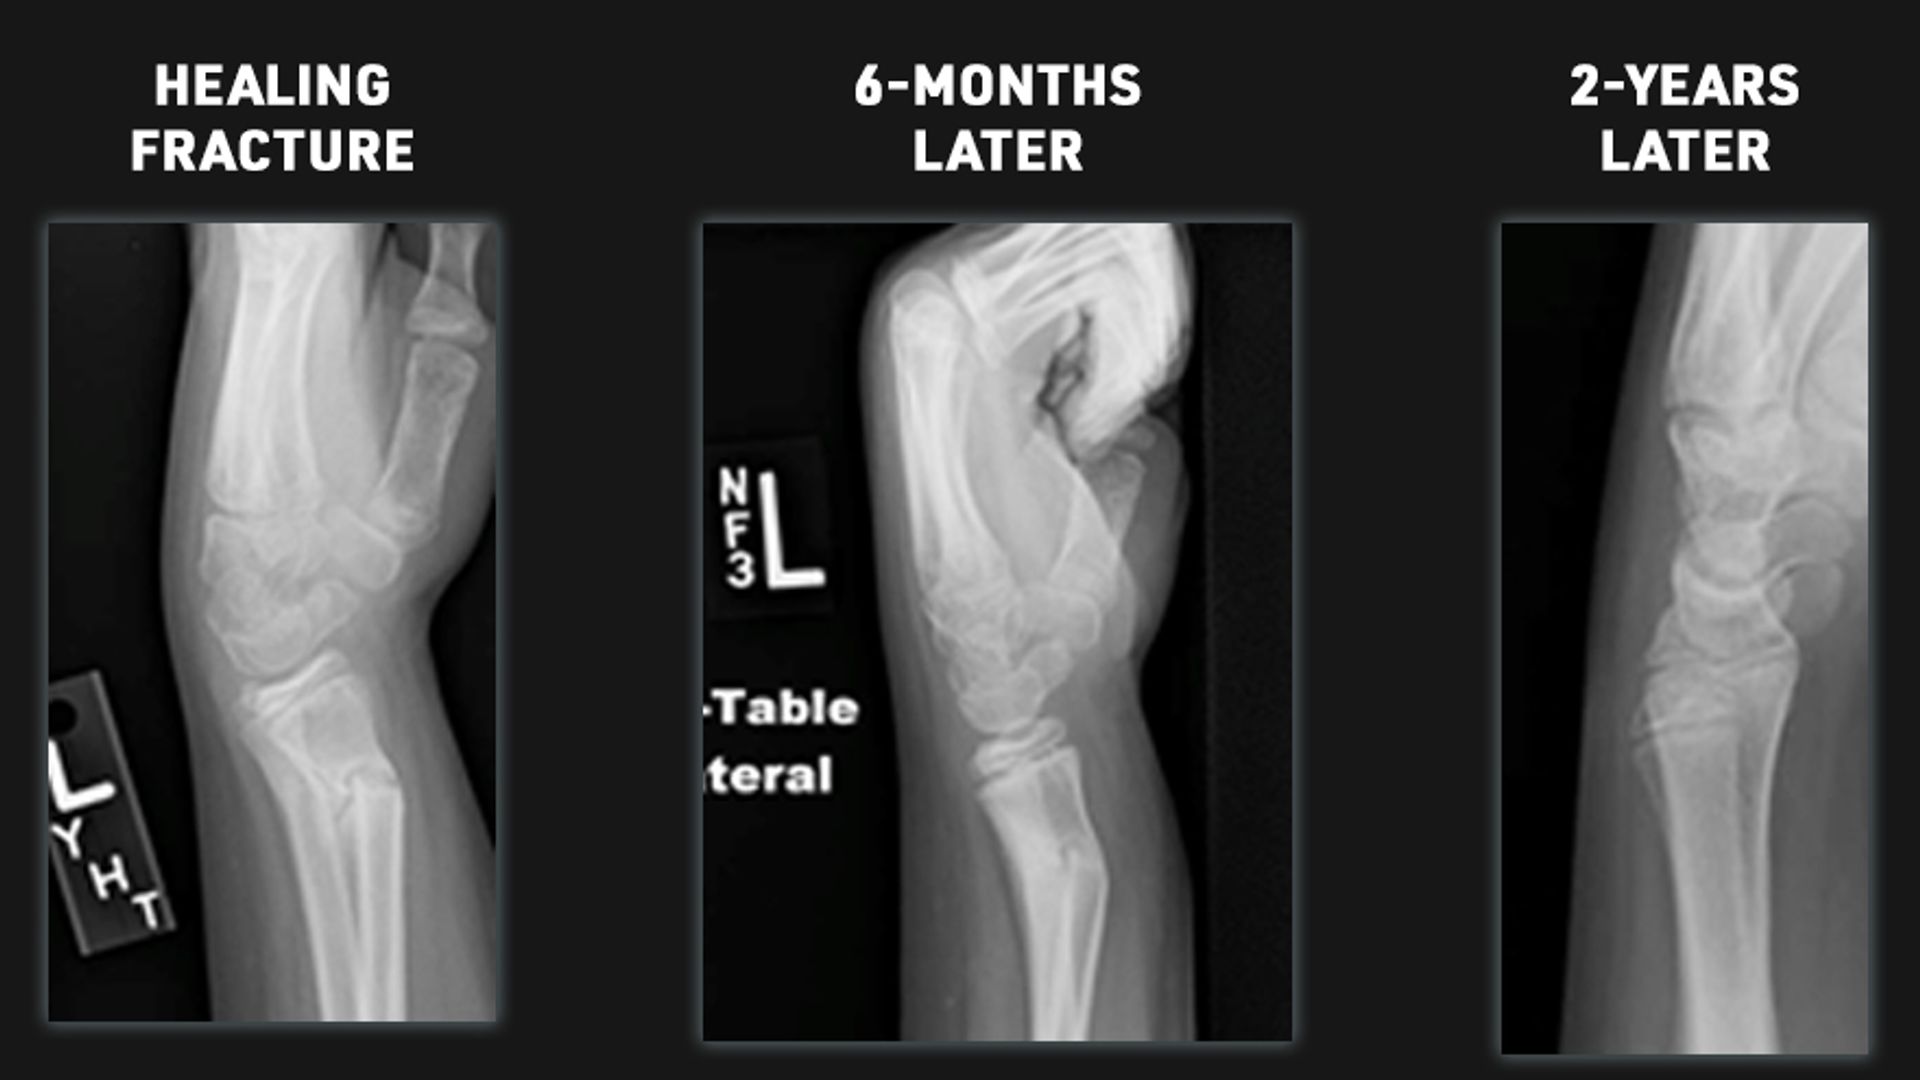

This is the area of the bone where growth comes from. These are located all over the body but typically at the end of the bones. Fractures to these areas can result in the bone growing abnormal. Because of potential for shortening of the arm or leg, or the bone growing crooked it is important for fractures in these areas to be followed closely and for up to 1-2 years or longer. It is better to identify a problem early. Small problems can be treated with small surgeries.

Because children are growing, unlike adults, their bones will remodel and straighten with growth. The amount of remodeling that will occur depends on the child's age, the bone fractured, and the fracture's location. In many cases, an angled bone will grow straight over the course of a year. For this reason, children's fractures should be followed by someone with experience in caring for children.